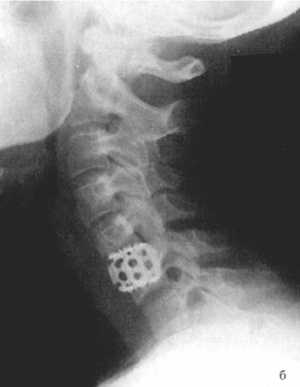

Рис. 3.5: а - травматический вывих С5-С6 позвонков;

б - межтеловая стабилизации металлическим цилиндром сразу после операции;

в - через 3 года после операции. |